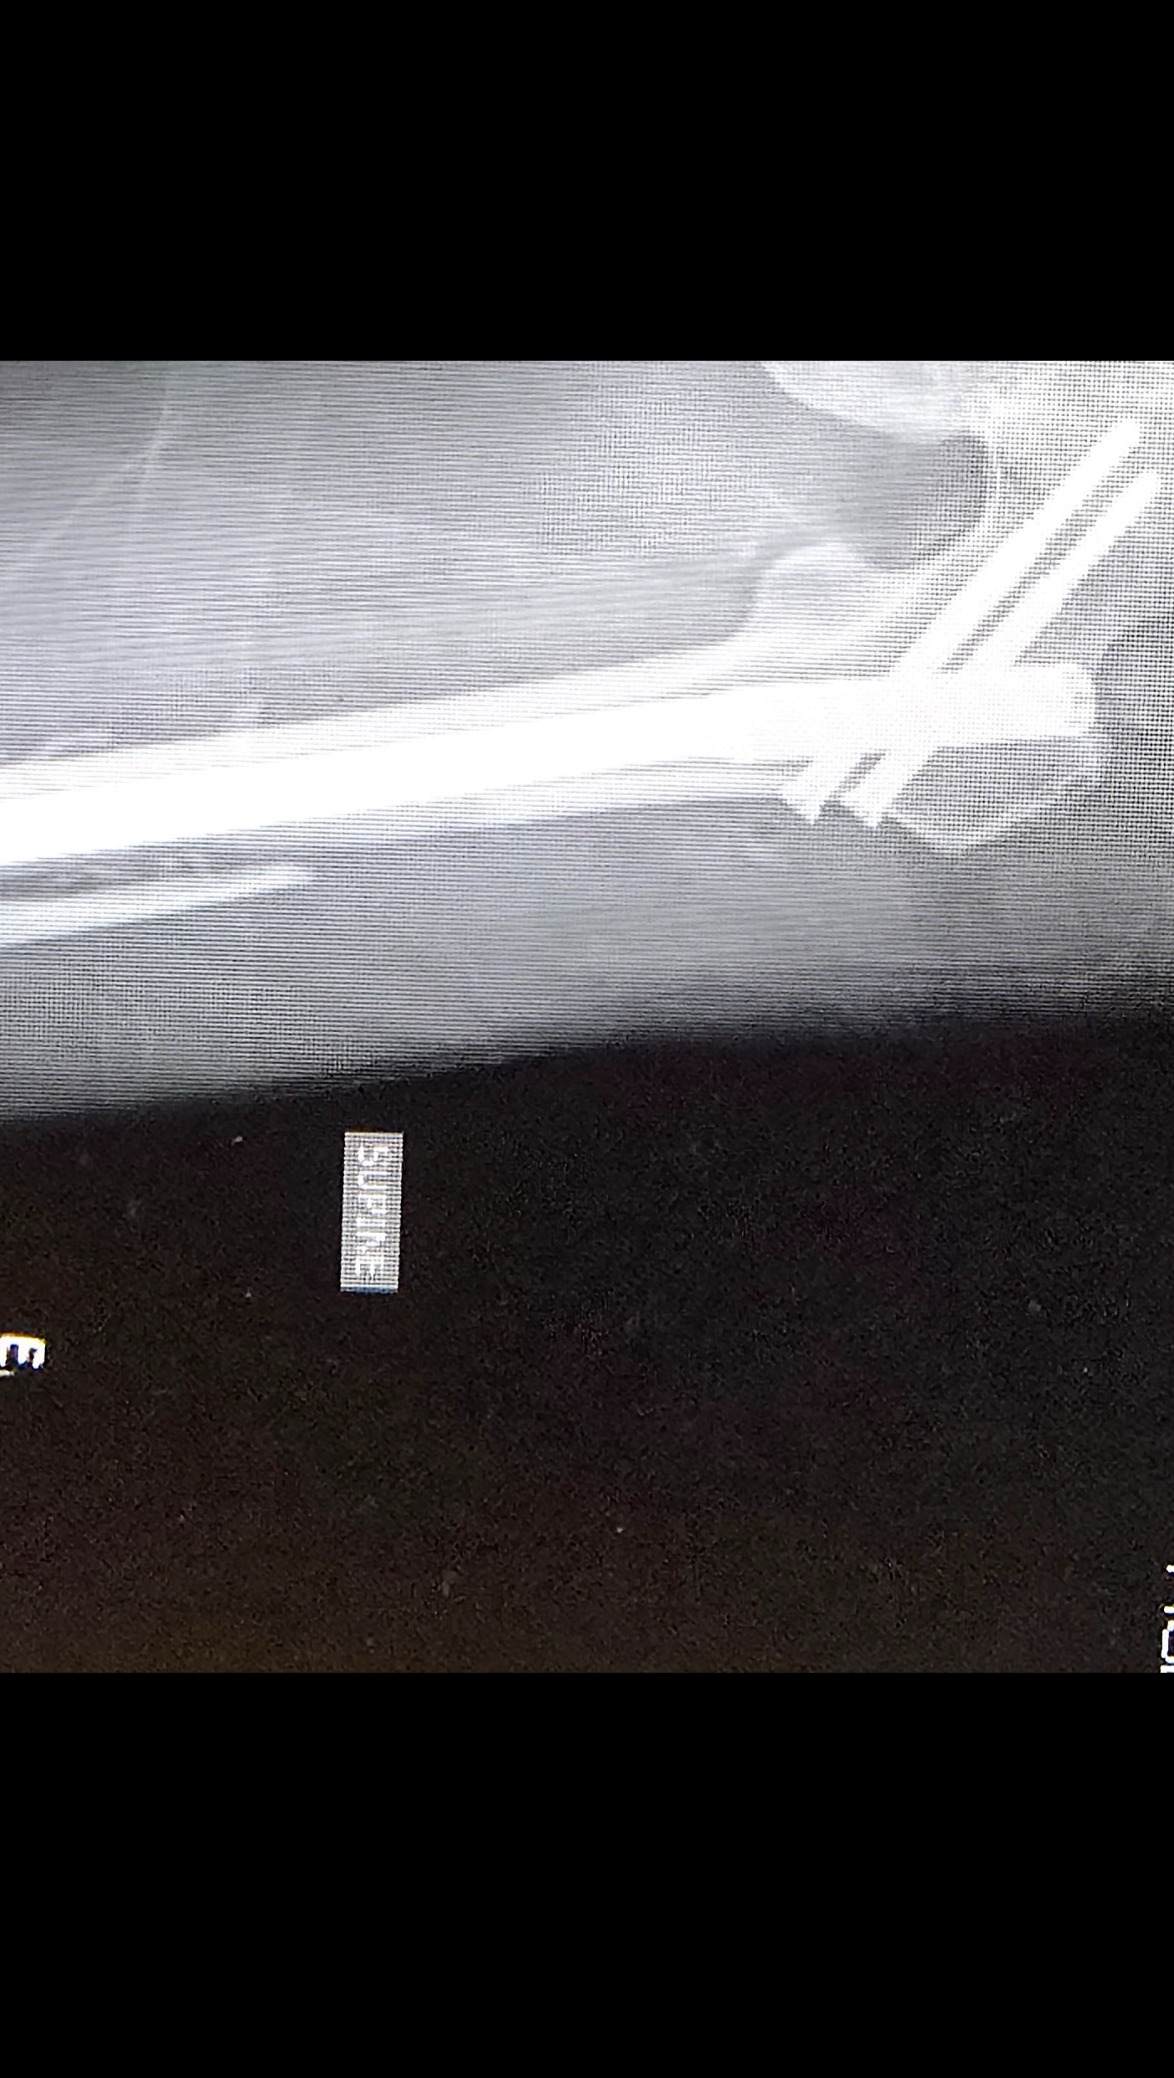

Even though he was wearing his seatbelt, the entire impact hit his left side. His left arm was shattered into multiple pieces, causing severe nerve damage. His left femur was broken into three pieces. He also struck his head against the window.

He was rushed to the hospital, where he spent a long night in unbearable pain before undergoing nearly eight hours of emergency surgery the next morning. Surgeons worked tirelessly to reconstruct his arm and leg. Today, Cole lives with metal rods and screws permanently placed in both his arm and leg.